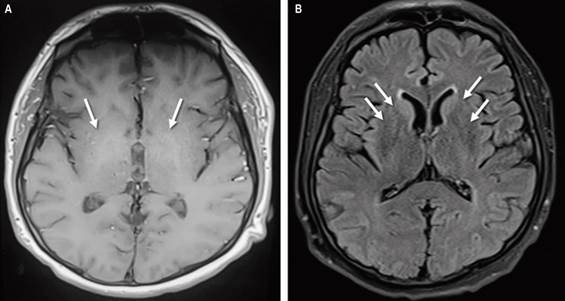

A lumbar puncture showed no abnormalities in the cytochemistry, a microbiological study for molecular infectious panel turned out negative for neuroinfection, and cytology and an immunophenotype did not exhibit suspicion of tumor involvement. Finally, a nuclear MRI was performed to observe hyperintensities in basal ganglia, bilateral caudate predominance in T1 sequences, and fluid-attenuated inversion recovery (FLAIR) suggestive of hepatolenticular degeneration (Figure 1).

The diagnosis to confirm or rule out ADH requires anamnesis, physical examination findings, blood analysis, and neuroimaging such as contrast-enhanced computed tomography, and, more usually, MRI, which allows the exclusion of other diagnoses such as brain hematomas, small vessel disease, and space-occupying lesions8. In ADH, MRI reveals changes in the basal ganglia with T1 hyperintensity, especially in the globus pallidus, a significant proportion in cirrhotic patients, related to the severity of the disease20. Laboratory tests can sometimes be helpful; however, it is worth mentioning that manganese levels in blood and urine indicate recent exposure (hours to days), but there are no biomarkers of cumulative exposure to manganese nor prognostic biomarkers of its neurotoxic effects. Therefore, they are not diagnostic.

In the case of suspected Wilson’s disease, ceruloplasmin and ammonia levels can be requested to rule it out. In our patient, they were negative, which, in addition to the absence of Kayser-Fleischer rings on physical examination, allowed us to reinforce the diagnostic suspicion, which was complemented by MRI findings of manganese deposits as a causal agent of encephalopathy19. Anyway, there is a good correlation between blood manganese levels and T1 hyperintensity observed by MRI, not necessarily correlated with neurological function, so the diagnosis is ultimately based on clinical suspicion and exclusion of more frequent causes without a diagnostic test confirming another etiology16,20.

Metabolic etiologies related to storage diseases were evaluated, obtaining a normal ferrokinetic profile. On the other hand, in the absence of standardized tests to measure manganese levels, normal ammonium and hyperintensities in the basal ganglia by brain MRI were vital in the differential diagnosis between Wilson’s disease and non-Wilsonian ADH, in favor of the latter, taking into account normal levels of serum ceruloplasmin and serum and urinary copper. The distinguishing characteristics of the two diseases are listed in Table 2.